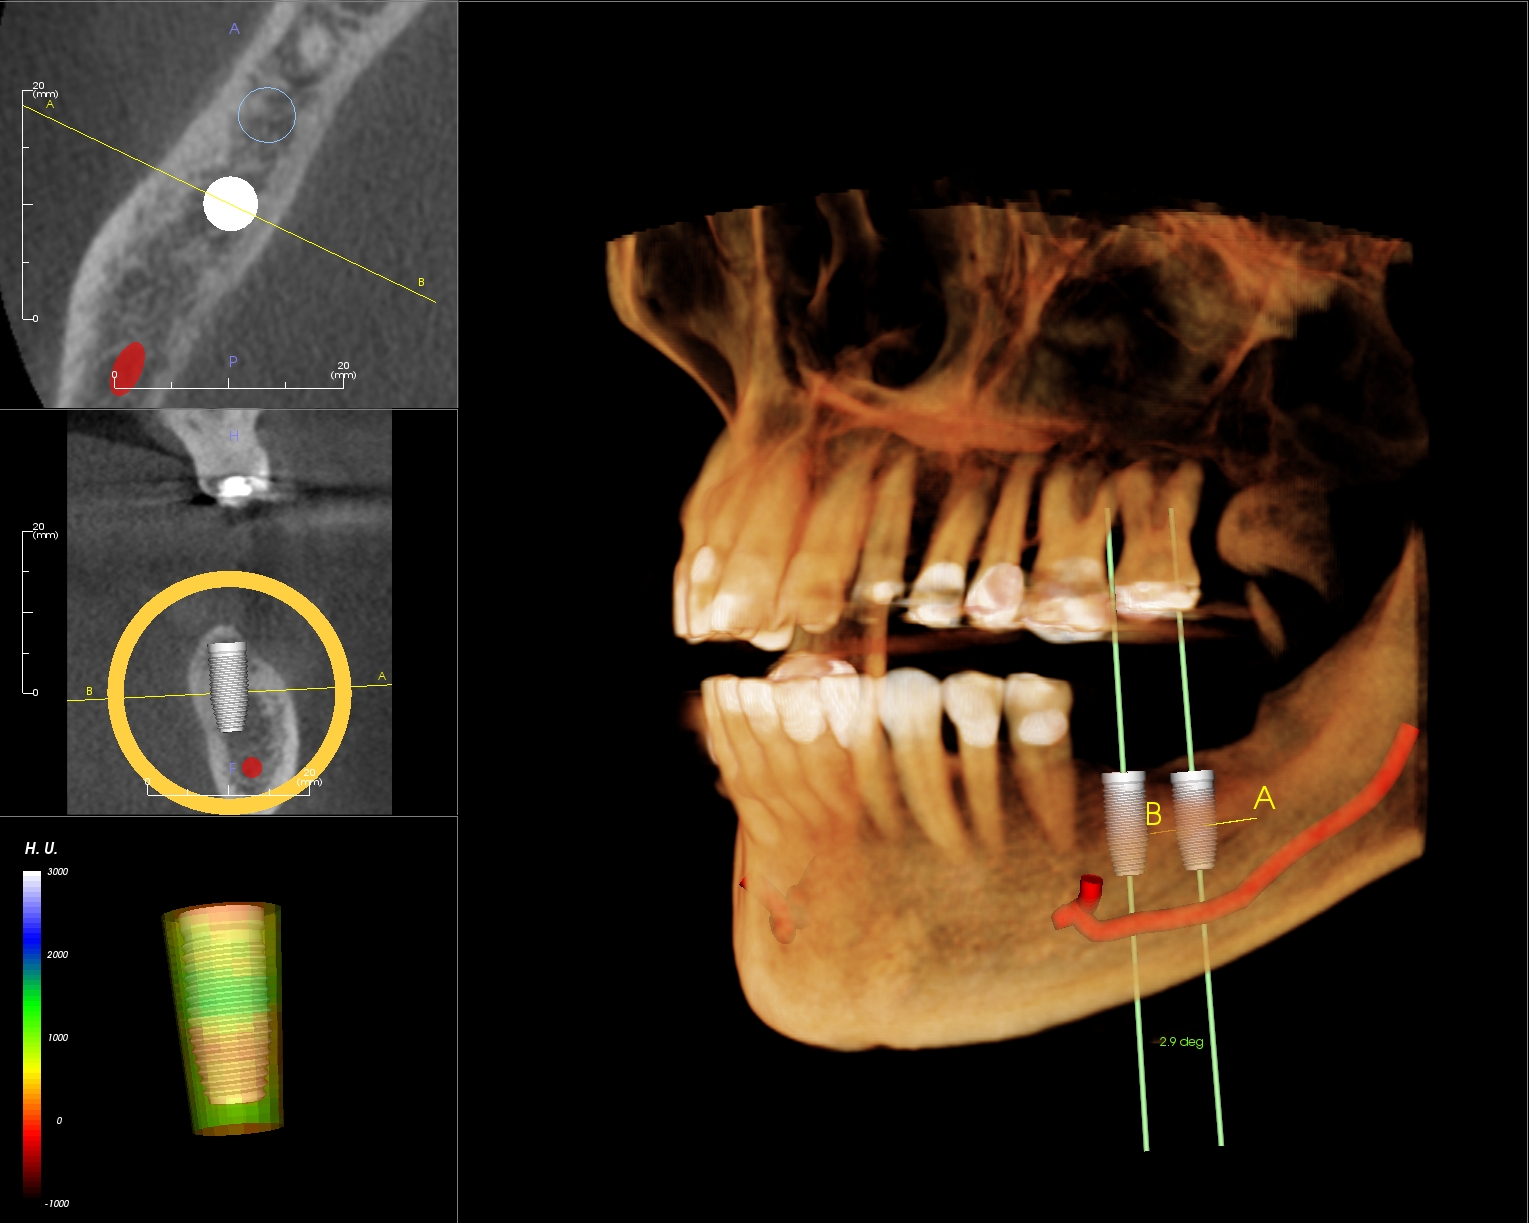

Cấy ghép implant: Cone Beam CT giúp chẩn đoán được tình trạng xương hàm, xác định kích thước và vị trí cấy trụ implant, ngoài ra, thông qua dựng ảnh 3D, bác sĩ có thể thực hiện cấy ghép implant mô phỏng trên phần mềm, từ đó giúp quá trình cắm ghép nhanh chóng và chính xác hơn.

- Khả năng tái tạo hình ảnh 3D, hỗ trợ bác sĩ phân tích và lên kế hoạch điều trị trong cấy ghép implant, chỉnh nha,…